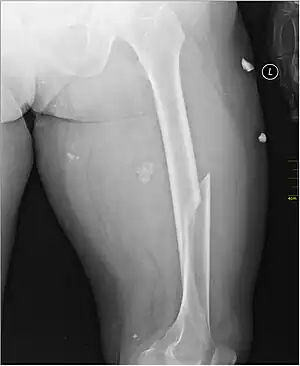

X-ray image of a femoral shaft fracture

A femoral fracture is a bone fracture that involves the femur. They are typically sustained in high-impact trauma, such as car crashes, due to the large amount of force needed to break the bone. Fractures of the diaphysis, or middle of the femur, are managed differently from those at the head, neck, and trochanter; those are conventionally called hip fractures (because they involve the hip joint region). Thus, mentions of femoral fracture in medicine usually refer implicitly to femoral fractures at the shaft or distally.

Anterior-posterior (AP) and lateral radiographs are typically obtained.[4] In order to rule out other injuries, hip, pelvis, and knee radiographs are also obtained.[5] The hip radiograph is of particular importance, because femoral neck fractures can lead to osteonecrosis of the femoral head.[4]